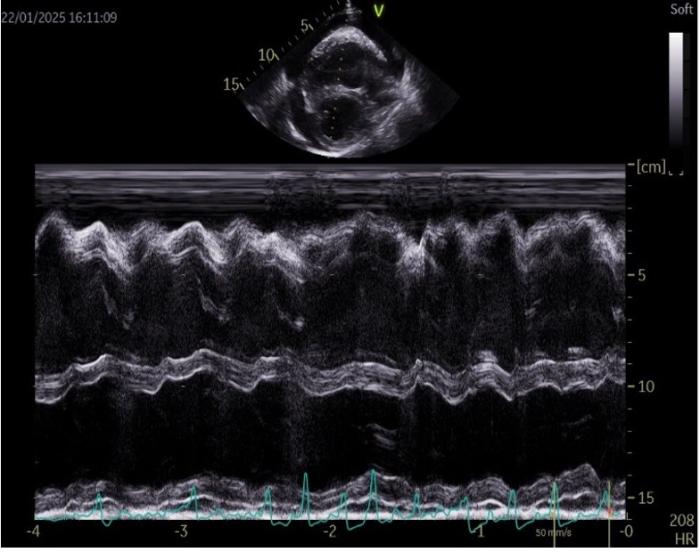

En el examen por Doppler color, se detecta flujo turbulento severo a nivel de la válvula tricúspide (Figura 4A) y moderado en la válvula mitral. A nivel de la válvula pulmonar se detecta una leve insuficiencia, aunque muestra una apariencia normal. Las velocidades aórticas se encuentran por encima del límite normal, con un valor de 2.23 m/s (referencia: <2 m/s). La función sistólica se encuentra disminuida, con una fracción de acortamiento (FA) del 13.77 % (referencia: 28-45 %) y una fracción de eyección (FE) del 29.34 % (referencia: 40-75 %) (Figura 4B).

Figura 4. (A) Examen con Doppler Color de la válvula mitral en un corte paraesternal derecho de cuatro cámaras en el que se aprecia la regurgitación mitral. (B) Modo M a nivel de los ventrículos mediante eje corto por ventana paraesternal derecha.